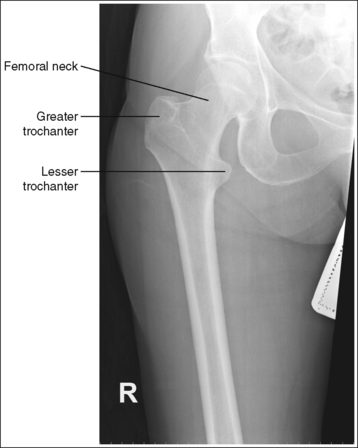

The distal femur demonstrates an AP projection. The medial and lateral femoral epicondyles are in profile, the femoral condyles are symmetrical in shape, and the tibia is superimposed over 0.25 inch (0.6 cm) of the fibular head.

Image density is uniform across the femur.

The distal femoral shaft is at the center of the exposure field. The distal femoral shaft and surrounding femoral soft tissue, the knee joint, and 1 inch (2.5 cm) of the lower leg are included within the collimated field. Any orthopedic apparatus located at the knee is included in its entirety.

The knee joint space is open but narrowed, and the anterior and posterior margins of the proximal tibia are superimposed.

• An open knee joint space is obtained when the anterior and posterior margins of the proximal tibia are superimposed. Because these margins slope distally from the anterior condylar margin to the posterior condylar margin, and the central ray is centered proximal to the knee joint, x-rays that diverge toward the proximal tibia are aligned close enough to parallel with the slope of the tibia to result in an open joint space. The joint space is narrower because the diverged x-rays project the distal femur partially into the joint space.